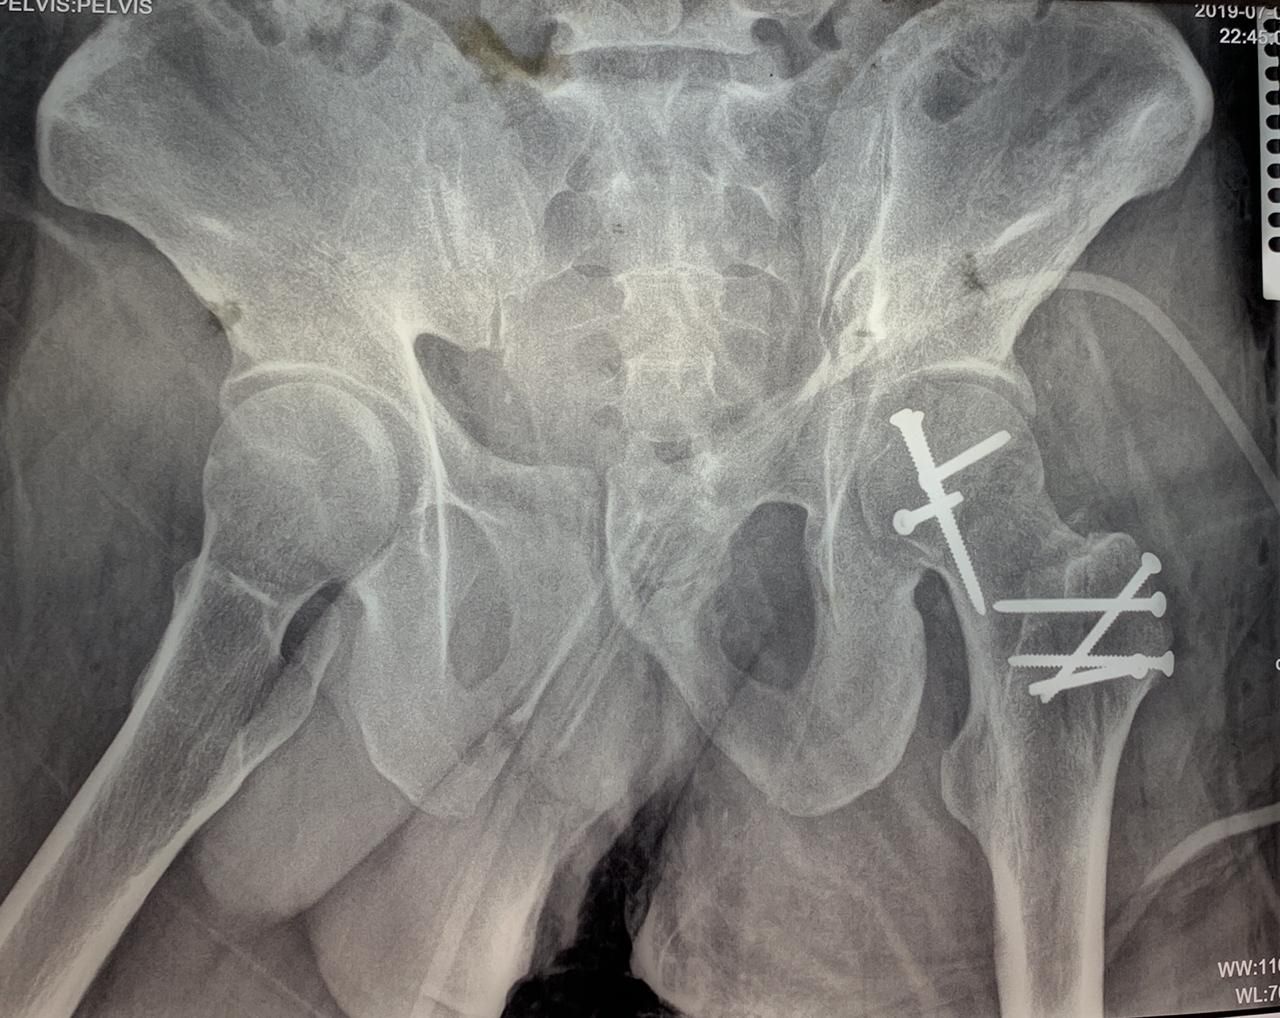

Cirugía ortopédica y traumatológica en el paciente politraumatizado (politrauma, pelvis y acetábulo). Cuenta UNAM Unidad Médica de alta Especialidad Hospital de Traumatología y Ortopedia Lomas Verdes IMSS

Master en Cirugía de Cadera y Pelvis (Miami Florida 2013)

Cirugía de Reconstrucción Complicada de Cadera, Pelvis y Acetabulo (Centro Medico Nacional de Occidente 2015)

• Reparación de fractura de anillo pelviano con abordaje doble